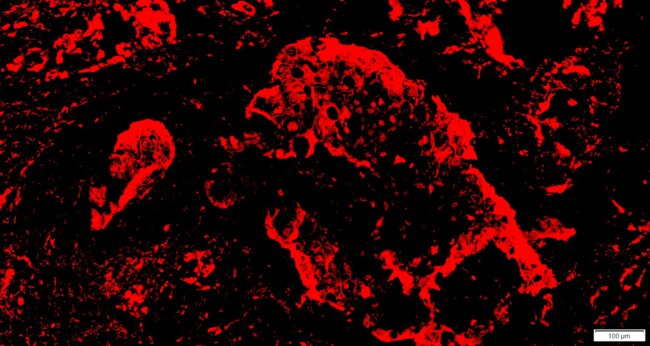

IF螢光染色

By

立众小編1號

2022-06-14